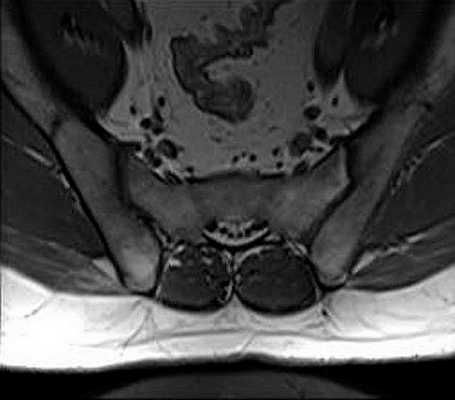

Томограмма сакро-илиальной зоны.

МРТ крестцово-подвздошных сочленений показывает:

состояние хрящевой ткани сустава;

скопление жидкости там, где ее быть не должно;

ширину суставной щели;

Для более точной диагностики сакроилеита используют контрастное усиление с препаратами на основе гадолиния. Средство улучшения визуализации МРТ крестцово-подвздошных сочленений позволяет рассмотреть воспалительные изменения, обнаружить признаки жировой дегенерации костной и соединительной тканей.